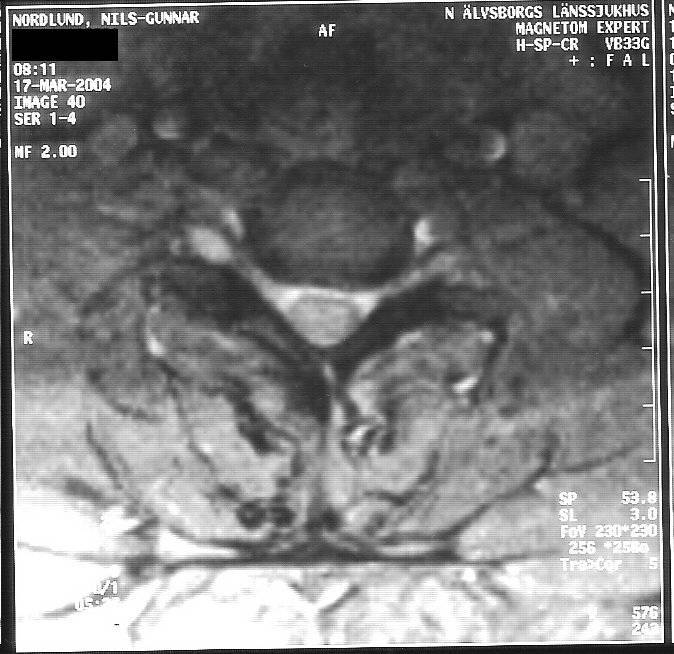

Jag bifogar även ett antal, av mig digitaliserade bilder från MR, 2004-03-17;

Bild 40.